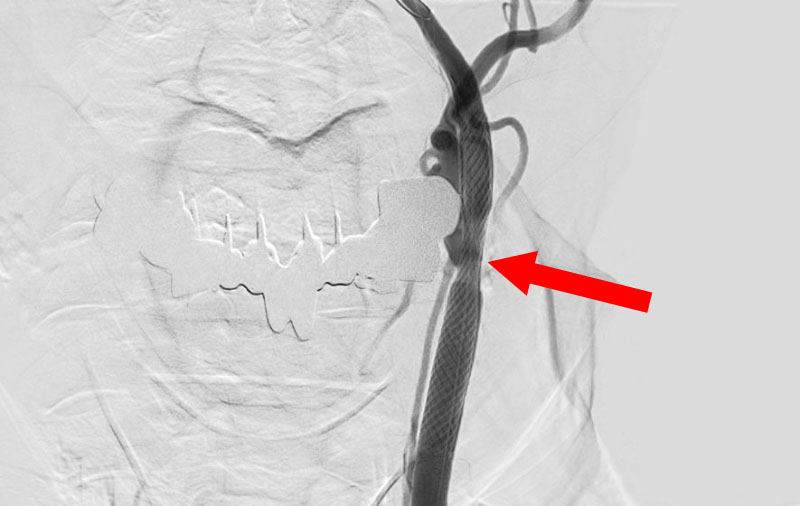

No.1590 手術中